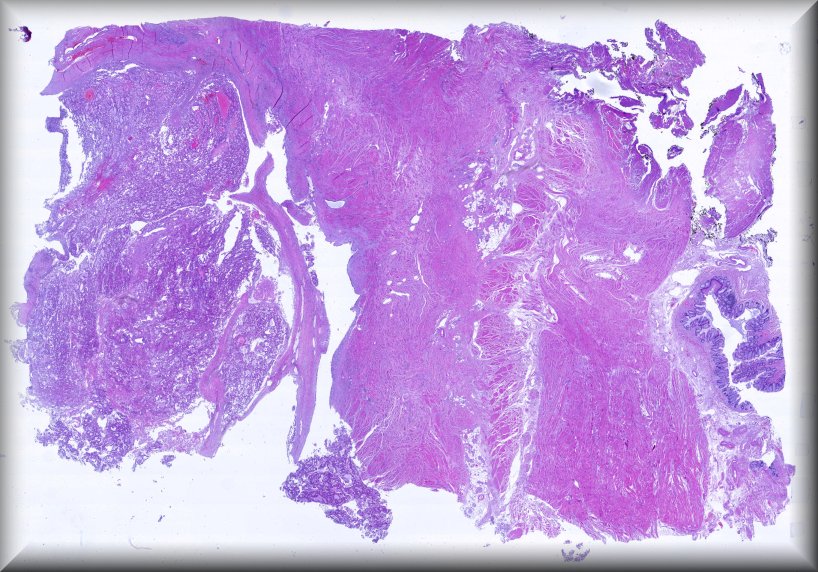

Mujer de 39 años en tratamiento de reproducciòn asistida por esterilidad y abortos de repetición, con antecedente de mioma subseroso variante de células atípicas tratado con ablación con radiofrecuencia y seguimiento espectante, con hallazgo de hidrosalpinx y varios miomas intramurales y sub serosos. Se realiza salpingectomía y toma de biopsia del mioma uterino de mayor tamaño con resultado anatomopatológico de leiomioma de núcleos atípicos por lo cual realizan miomectomía para estudio histológico completo de toda la lesión

Preparacion virtual

Visor HTML5

Visor NZH

Diagnóstico